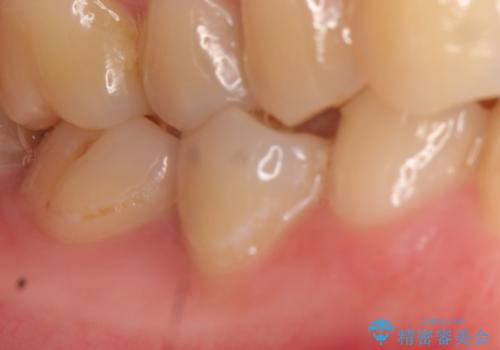

- 右下の奥歯がズキズキ痛むので診て欲しいといらっしゃった方の症例です。

右下5は虫歯が大きく神経は保存不可能だったため、根管治療を行った後、オールセラミッククラウンによる補綴を行いました。